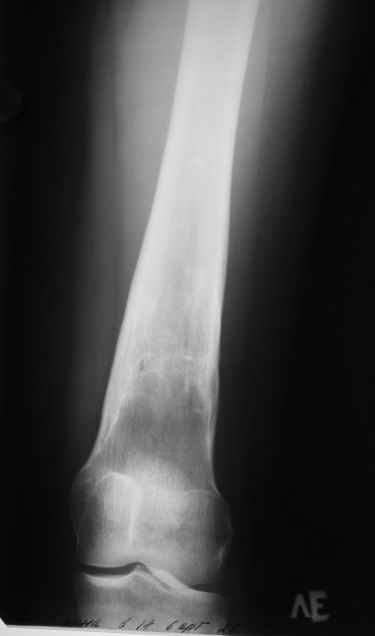

Пациентка 23 лет, доставлена в клинику с Диагнозом: Закрытый сегментарный оскольчатый перелом левой бедренной кости в верхней и средней трети. Травма в результате ДТП 10.03.2006г. Из анамнеза у пациентки диспластический левосторонний коксартроз, S-образный сколиоз 2ст. В 1999г в Кургане выполнялась остеотомия бедра в нижней трети и коррекция укорочения конечности на 3 см (рентгенограммы бедра и таза до травмы в приложении). До получения травмы пациентка ходила без боли с полной нагрузкой на левую ногу. Учитывая дисплазию левого ТБС, пациентке, вероятно, предстоит операция тотального эндопротезирования лев ТБС, что требует анатомичного восстановления проксимального отдела бедра.

Рассматриваются следующие вариант остеосинтеза: 1) Экстракортикальный остеосинтез проксимального и дистального перелома пластиной с угловой стабильностью типа LISS( г Рыбинск);

2) Ретроградный интрамедуллярный блокированный остеосинтез дистального перелома и накостный синтез проксимального пластиной с угловой стабильностью;

3) Остеосинтез бедра в аппарате внешней фиксации с фиксацией таза и возможной открытой адаптацией фрагментов.